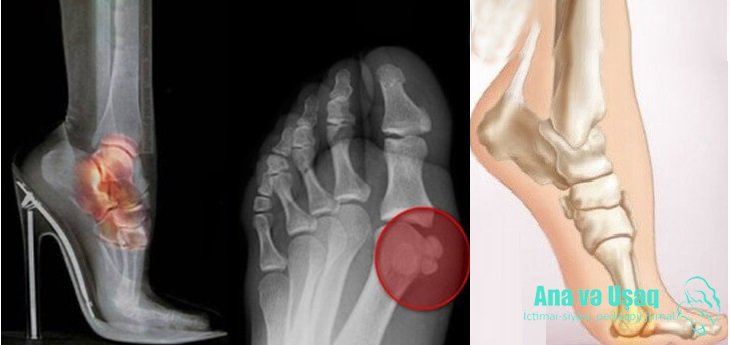

Hündürdaban ayaqqabılar bədəndə bir forma pozğunluğuna səbəb olmaqla yanaşı, gün ərzində ayaqları daha 6 km getmiş qədər daha əlavə yorğunluqla yükləyirlər. Dikdaban ayaqqabılar dırnaq batması, ayaq baş barmağının içə doğru əyilmiş dayanması, döyənək, göbələk infeksiyası yaradır.

Barmaqların sürtünməsi nəticəsində dərinin sərtləşməsi baş verir.

Barmaqların və dırnaqların yataqlarına davamlı bir təzyiq düşdüyü üçün dırnaq yapışması və göbələk fəsadları yaradır.

Baş barmaq böyük bir təzyiqlə ayaqqabının ucuna itələnir, barmaqlar amorf şəklində qıvrılır, barmaq bükülmələrinin ortasında deformasiya baş verir. Xüsusilə belə bir təzyiqdə ayaq və barmaqlarda çox ciddi bir ağrı əmələ gəlir.

Dizlərdə kirəçlənmə yaradır. Hündürdabanlı ayaqqabılar cismin ağırlığının mərkəzini irəliyə daşıyır, nəticədə insan balansını itirir, ayağını bükür və ayaq biləklərində ağrılar, xüsusilə diz və bel ağrıları üzə çıxır və s.